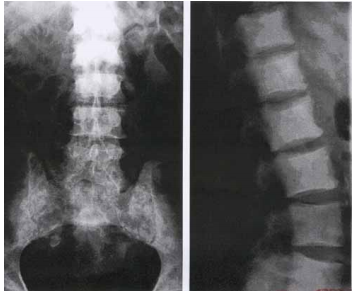

75 75 歲女性病患,背部疼痛多年,最近 3 個月加劇,經影像檢查除了主動脈鈣化明顯外,腰椎及椎體 也有變化;圖 A 為腰椎側面 X 光攝影,圖 B 為電腦斷層掃描之橫切面。這位病患最可能的診斷為何?

(A) 感染性脊椎炎 (B)癌細胞骨轉移及病理性之壓迫性骨折 (C)骨質疏鬆症之壓迫性骨折 (D)外傷性壓迫性骨折